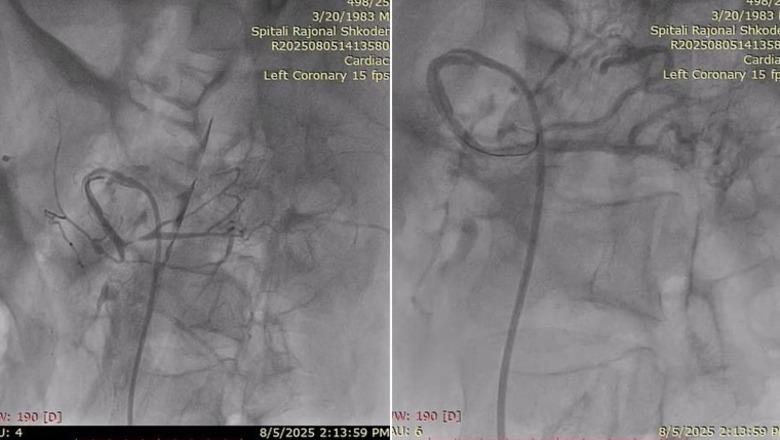

Bëhet fjalë për stentimin e arterieve mesenterike superiore, një ndërhyrje komplekse që trajton isheminë kronike të mezenterit, një sëmundje me një shkallë të lartë vdekshmërie.

Ministria e Shëndetësisë dhe Mbrojtjes Sociale, Albana Koçiu thotë se ndërhyrja u realizua me metodë endovaskulare, falë bashkëpunimit të ngushtë mes kirurgëve vaskularë dhe hemodinamistëve.